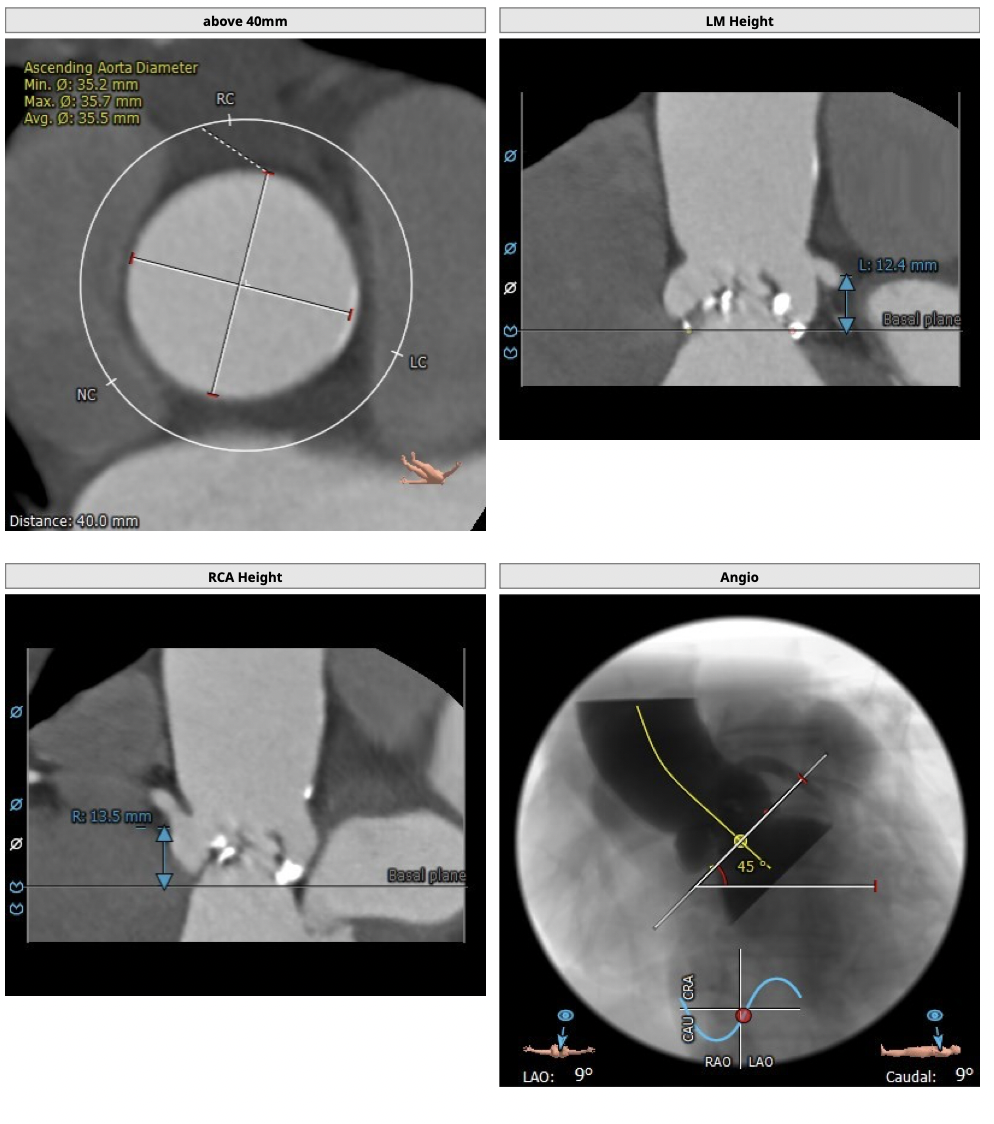

主动脉CT

图片

手术策略

CT分析:

*患者为TYPE1型二叶瓣,左右钙化融合,冠脉高度高,法式窦结构可,心脏角度约50°,左室大小可,心肌增厚,升主动脉未见明显增宽。主动脉弓部走形较平缓,右侧股动脉可作为主入路。

制定策略:

经分析研判,拟从右侧股动脉穿刺入路,使用23mm球囊预扩,选用L29号的VenusA-Valve瓣膜,采用VenusA-Plus可回收输送系统进一步确保手术安全,瓣膜释放后结合造影和超声情况,决定是否后扩。